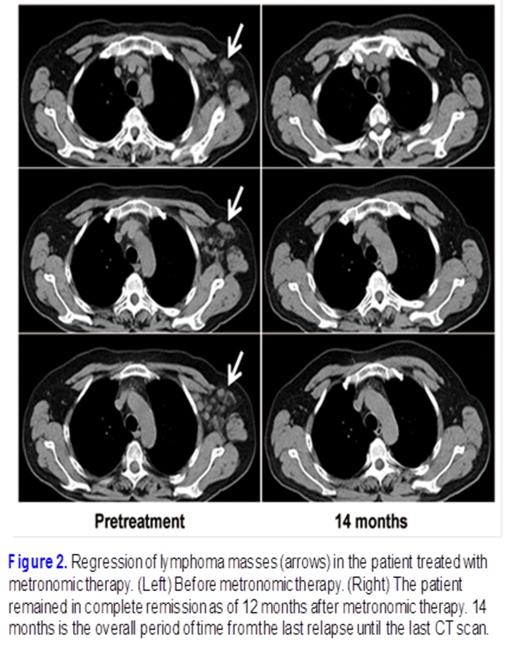

The prognosis of ALK-positive, anaplastic large cell lymphoma is usually favorable, but patients that are resistant to primary chemotherapy or who relapse early have always been associated with an aggressive clinical course and unfavorable prognosis. For a recurrent relapsing case of ALK-positive, anaplastic large cell lymphoma heavily pretreated by nearly 50 cycles of chemotherapeutic agents (Fig 1.), we developed a treatment schema of metronomically scheduled low-dose methotrexate, which successfully controlled the relapse more than 12 months (Fig. 2). The metronomic therapy that we identified from this case was an effective and economic option that caused less damage to other organs than other treatments; thus, it should be given consideration for the treatment of similar cases, especially in the setting of where the recurrence seems to be only skin disease or when other effective regimens are unavailable. Our study represents the first report of a well-documented case of ALK+ALCL which was refractory to various lines of therapy but which was subsequently successfully treated with a combination of prednisone and etoposide followed by low-dose MTX maintenance metronomic therapy.